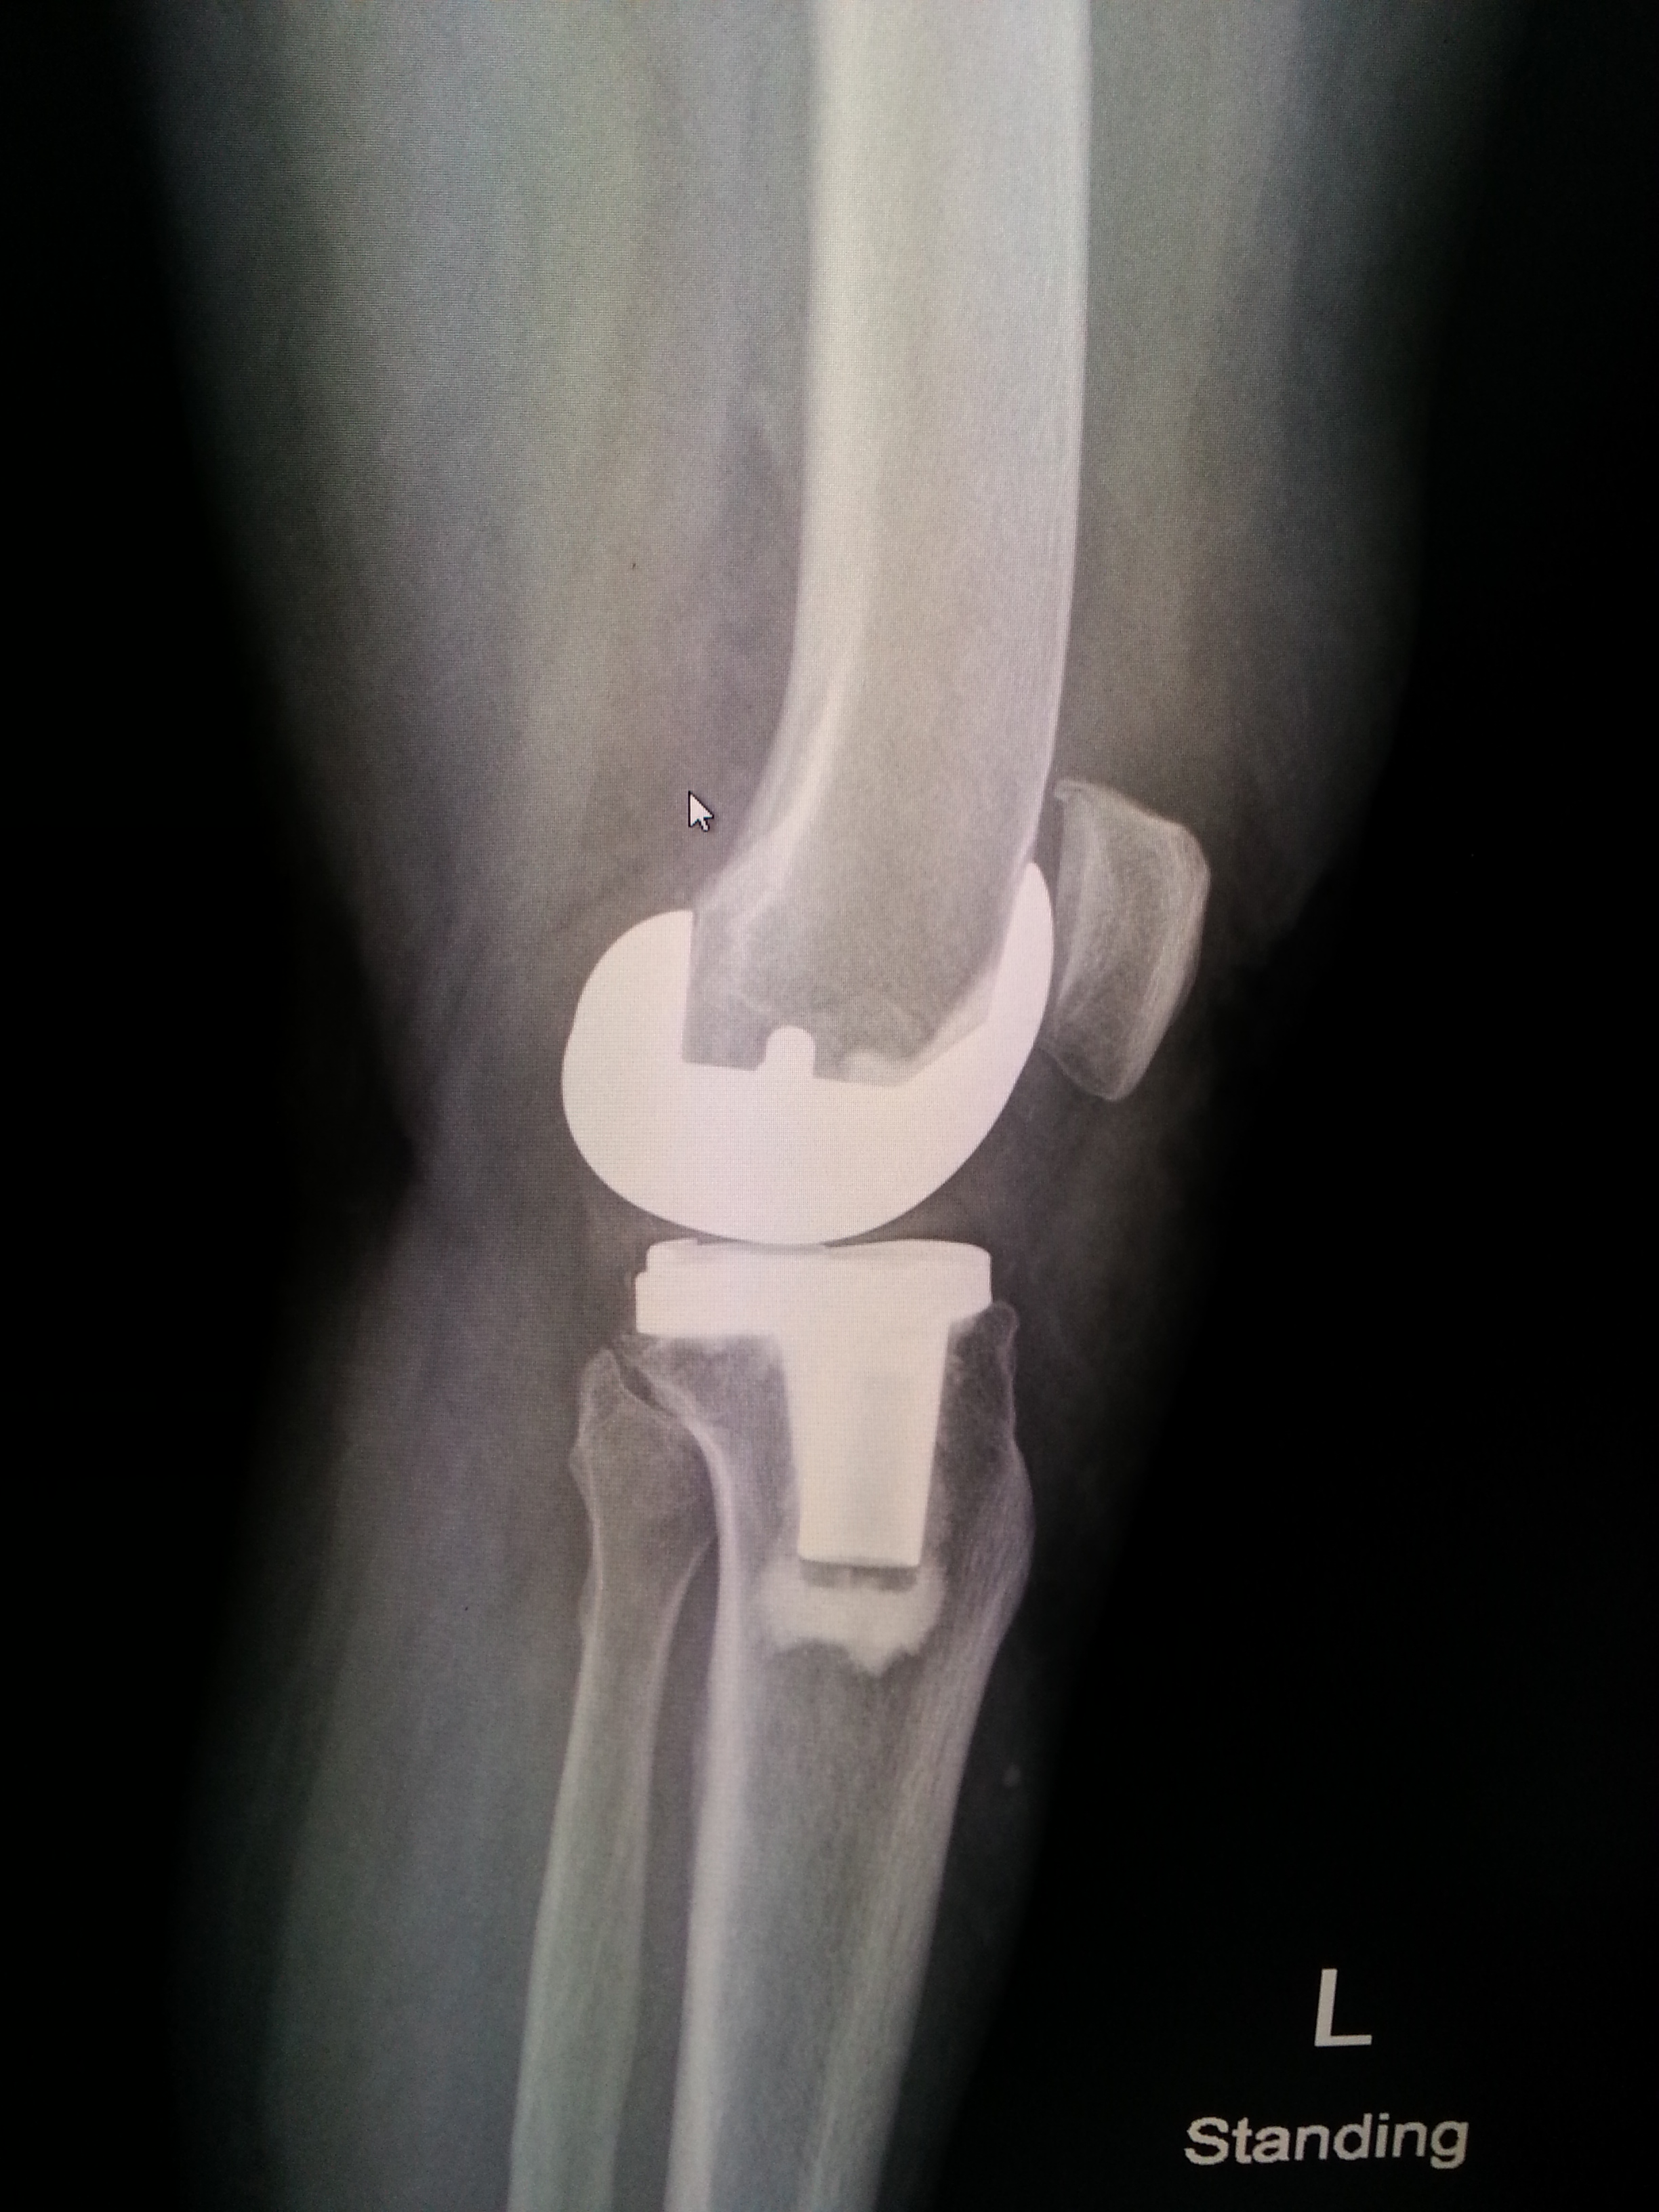

ฟิล์มเอ็กซเรย์ก่อน (ภาพซ้าย) และหลัง (ภาพขวา) ของการผ่าตัดข้อเข่าเทียม ส่วนก้อนสีขาว ๆ ของภาพทางขวามือ คือข้อเข่าเทียมที่ใส่เข้าไป

วันนี้คุณหมอนัดตรวจและมี X-Ray สภาพข้อเข่า เช็คการพับงอ ทุกอย่างผ่านไปด้วยดี (ต้องยกผลงานให้คุณหมอเลย เก่งมาก ๆ )